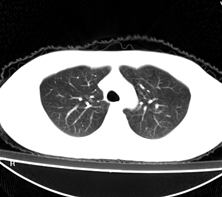

病人为一考上研究生的学生,健康体检发现。请踊跃发表意见。

左肺上叶见后段近侧胸壁见两个薄壁空洞影,洞内无液平,考虑肺囊肿,因为肺囊肿位于肺的外周,囊肿与支气管相通,囊壁薄,囊内无液性成分。以上使我的观点,原与各位交流

左肺上叶尖后段胸膜下可见两个类圆形薄壁空洞,内外壁较光滑,腔内为气体密度,支持结核性薄壁空洞。

我想应是肺囊肿,因为边界清晰,其内无液平面,周边没有卫星灶,还有临床也不支持肺结核

临床无症状,左上肺两枚厚壁空洞,内无气液平面,周围未见卫星灶,囊肿可能大,建议追问病史。请各位老师指正

左飞上叶尖后段两个含气的囊性肿块,边界清晰,其周围未见卫星病灶,考虑肺囊肿.不支持肺结核是因为未见卫星灶,临床未见体征.

左肺上叶后段见两个孤立圆形厚壁空洞,无液平及壁结节。周围清晰,无卫星灶。结合病史,如此大的病灶病人毫无感觉,另外周围如此清晰,应能排除结核空洞;肺囊肿壁应更薄,如合并感染可增厚,但周围应模糊。本人考虑:肺韦格肉芽肿。

左肺上叶后段见两个孤立圆形厚壁空洞,无液平及壁结节。周围清晰,无卫星灶。结合病史,如此的病灶病人毫无感觉.考虑1肺部感染[注意新隐球菌感染----中华放射学杂志---2006----第一期-----104页]。2肺囊肿。请指教!!!

左上叶尖后段可见两个中等壁厚空洞,腔内无液平,内外壁光整,局部轻度胸膜增厚,首虑结核。

考虑肺囊肿可能性大。不支持结核是因为周围肺野内未见明显卫星灶及纤维索条,不支持韦格氏肉芽肿是因为内壁及外壁均很光整,壁厚薄一致,而韦格氏肉芽肿洞壁厚薄多不均匀,内壁多不规则,其内可有形态不规则的内容物。

左肺尖后段的两个薄壁(纵隔窗)含气囊样病变,壁厚薄较均匀、光整、内无液气平形成、其邻近肺野见

少许渗出、未见卫星灶,其余肺野未见明显支气管播散灶(楼主虽然未上传全其他层面图片,但认为因正常而未上传)。

综合上述:考虑为肺囊肿合并感染,不支持结核空洞(虽然病变位于结核好发区,但认为这么明显的结核空洞应该有明显的肺内支气管播散灶)。